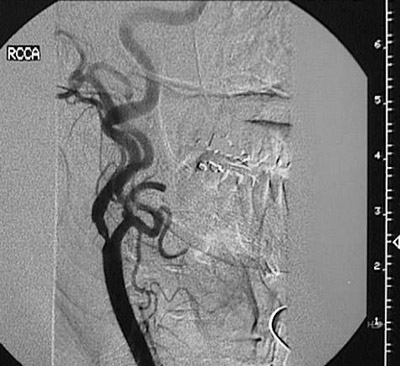

There is atherosclerotic narrowing in this right internal carotid artery as seen on angiogram.